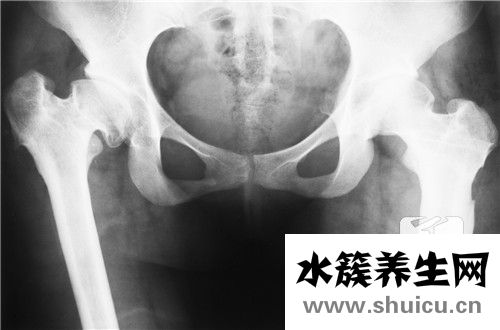

盆底肌并不是一塊肌肉,而是封閉骨盆底的肌肉群。

由一對(duì)肛提肌和一對(duì)尾骨肌構(gòu)成,這一肌肉群猶如一張“吊網(wǎng)”尿道、膀胱、陰道、子宮、直腸等臟器被這張“網(wǎng)”緊緊吊住。

當(dāng)盆腔肌肉功能正常時(shí),這張網(wǎng)通過(guò)這些結(jié)構(gòu)的收縮和緊張來(lái)抵抗腹壓增加,從而支撐盆腔臟器。